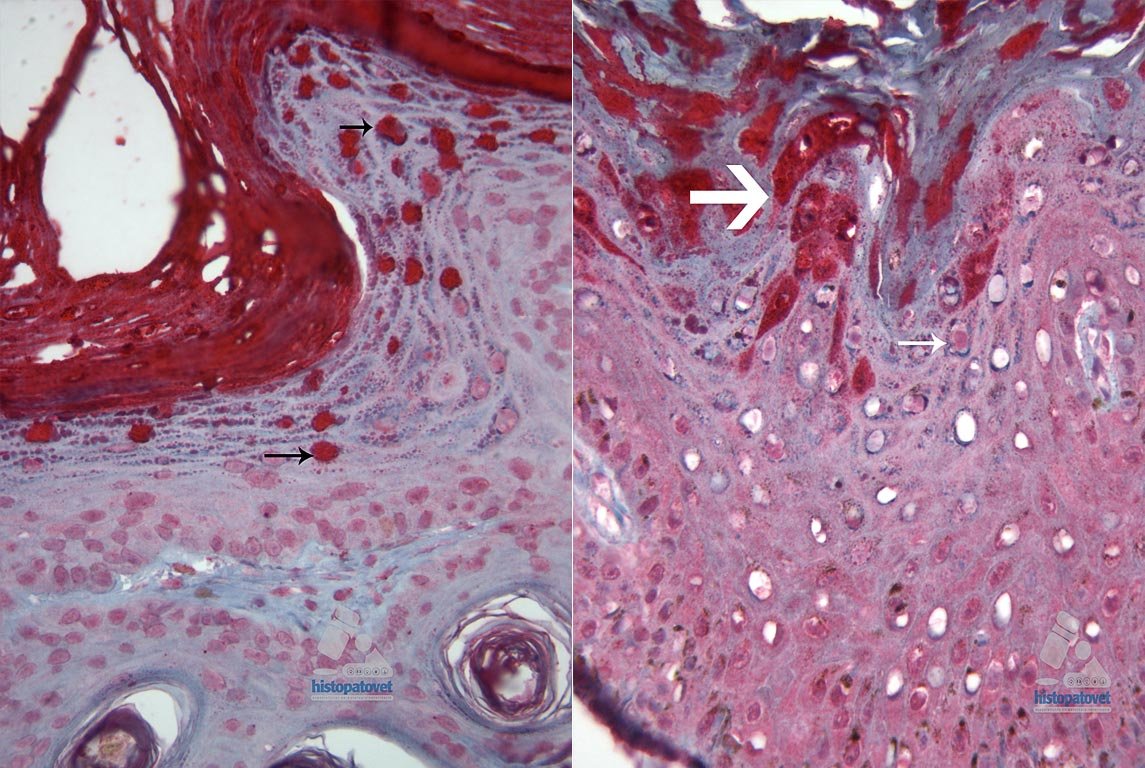

Ingresa a consulta por una lesión única cutánea(piel), de aproximadamente 0.50 cms de diámetro, localizada a nivel costal. Evolución: los dueños no pudieron precisar el tiempo de evolución. Estudio Patológico: Se recibe una biopsia quirúrgica(helicoidal) de cerca de 1.0 cm de diámetro, con un nodulito oscuro en el centro de unos 0.30 cms. Diagnóstico Histopatológico: Se trata de una dermatopatología conocida como PLACA DÉRMICA PIGMENTADA, la cual muy probablemente sea causada por un papilomavirus. Ver Fig. 1. Y Fig.2.

Fig.2. Acercamiento del estrato espinoso. La flecha señala una posible inclusión viral.Comentario: Para poder establecer su etiología es necesario realizar una prueba de inmunohistoquímica en parafina, técnica no disponible en Costa Rica. NOTA: Unos meses después, la prueba se realizó en el Diagnostic Center for Population & Animal Health Michigan State University, dando positiva. Ver Fig. 3-A-B.

Fig.3-A-B. Las flechas indican varias células (núcleos positivos).Definición de Placa: Es una lesión firme, sobre elevada, con una superficie lisa, provocada por un engrosamiento de la epidermis( estrato corneo y espinoso). Su diámetro es generalmente mayor a un centímetro. Las placas, forman parte del grupo de las lesiones primarias dérmicas. Ver siguiente ilustración.